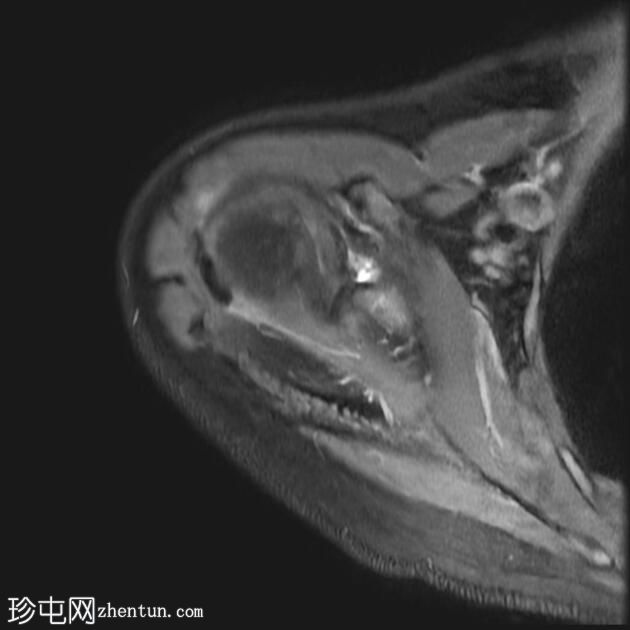

MRI

冠状位

T2加权像

T1加权像

冠状位PD加权像

脂肪抑制像

矢状位

PD加权像

肩袖钙化性肌腱炎:冈下肌腱上部纤维可见约7 x 14 mm的低信号病灶

冈上肌腱滑囊侧纤维可见轻度增高液体信号,提示肌腱病

肩峰II型

肩峰下滑囊可见轻度液体信号